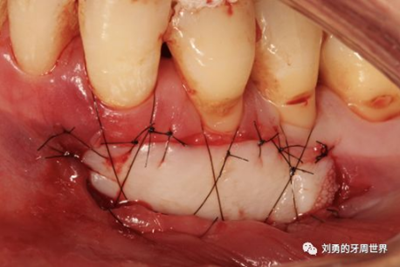

比如strip技術(shù),如下圖:

上圖中,種植體唇側(cè)缺乏附著齦,從上腭取瓣,常規(guī)做法:取長(zhǎng)而寬的齦瓣,這樣供區(qū)面積大,術(shù)后疼痛重。

為了減少痛感,從雙側(cè)上腭取多條長(zhǎng)而窄的齦瓣進(jìn)行移植,這樣每個(gè)供區(qū)的傷口都比較窄,可以減少術(shù)后的痛感。